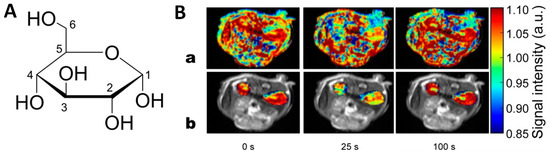

Recently, a new class of T2-agents, T2-exchange (T2ex) agents, have been explored. T2ex-agents are usually small molecules, similar to the Gd3+ agents already in clinical use, and provide some advantages over the conventional iron nanoparticles [13,14,77]. The effect arises from the chemical exchange of protons that exchange differently from the bound water and at an intermediate pace—slower than that required for a common T1-agent (see Figure 3). To the best of our knowledge, so far, none of the inorganic T2ex-agents have been successfully applied in vivo. However, some progress has been demonstrated with diamagnetic molecules containing exchangeable –OH groups, as it is the case that glucose and maltose showed accurate detection of hyperglycolytic tumor regions in a mouse model (Figure 8 and Table 2) [78,79].

Figure 8.

(A) Haworth projection of d-glucose. (B) Transverse relaxation data from a dynamic in vivo glucose infusion experiment on a mouse. T2-weighted images of mouse kidneys from the time of a glucose bolus infusion are displayed (time indicated below each image). (a) Effects in all regions displayed. (b) Only kidney signal displayed in color on grayscale image to highlight effects. Adapted with permission from [78].